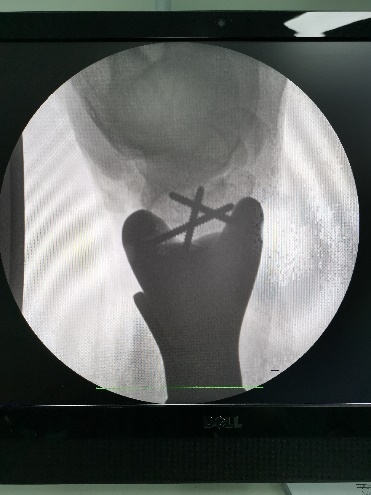

术中透视

1月20日,在麻醉科的协助之下,与祁伟仲博士,骨科赖少勇医生一起经历了两个半小时的努力后,林荔军主任和他的团队成功地将肿瘤切除,并为江某换上了这条3D打印个性化定制的“新腿”。现患者恢复顺利,已可在拄拐辅助下行走。